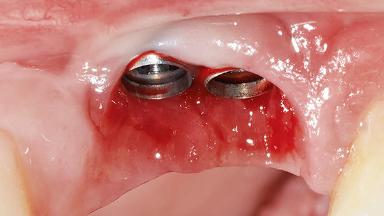

GBR and Soft-Tissue Augmentation Following Explantation to Rehabilitate a Soft- and Hard-Tissue Defect

It is sometimes necessary to remove and replace compromised implants. This case is a clear example of the need for multiple steps to achieve an optimal therapeutic result for patients with non-salvageable implants. It illustrates how the lost soft and hard tissues were rebuilt in a sequence that improved the healing of the hard tissues and assured their long-term stability. The 35-year-old healthy patient presented with clinical attachment loss on the proximal and lingual surfaces of the natural dentition. Some gingival recession was present on natural teeth, particularly in the posterior sextants (S1, S3, S4, and S6).